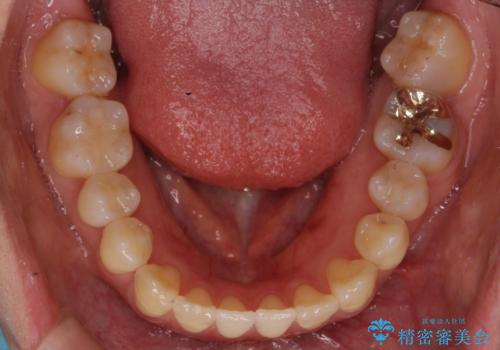

前歯のがたつき 若干受け口 インビザラインで

治療症例の内容

- 前歯のねじれおよび下の前歯が前に出ていることを気にして来院。

インビザラインで治療をおこないました。

前歯のねじれもなおり、比較的短期間でご満足いただけました。

部分矯正コースでしたので左下67の段差は特に治しておりません。

右下567及び左下6の虫歯治療も一緒に行っています。